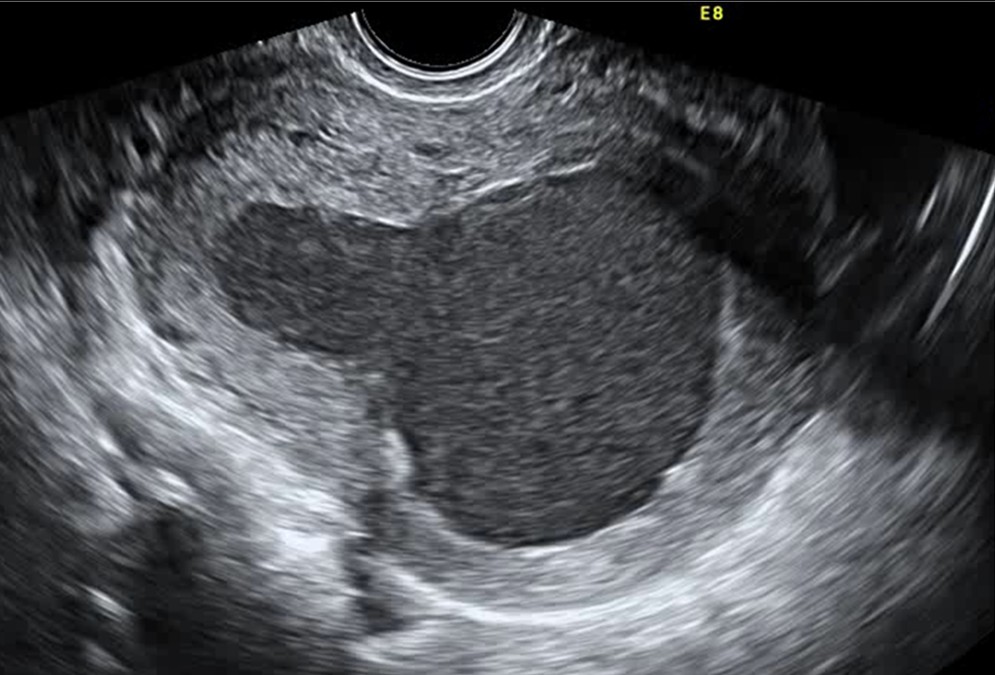

Пацієнтка, 41 рік, звернулася до лікаря-гінеколога медичного центру «Мати та дитина» — Поліщук Ольги Іванівни через затримку менструації.…